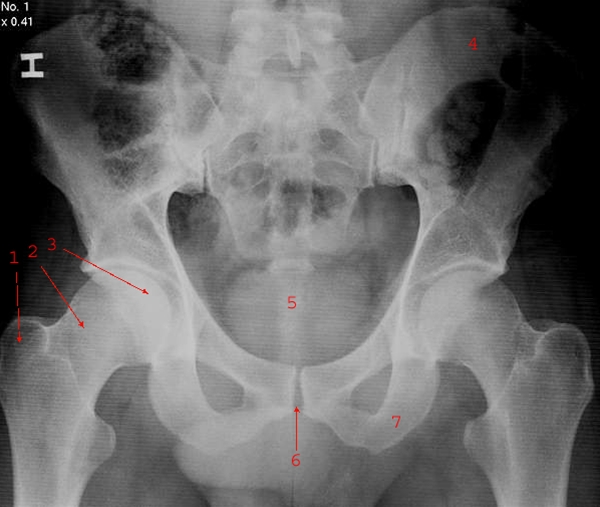

Normalt frontalbillede af bækken med sacrum (korsben) og hofter

1. Trochanter major

2. Collum femoris (lårhals)

3. Caput femoris (ledhoved)

4. Os ilium

5. Os coccygis

6. Symfysen

7. Os ischii